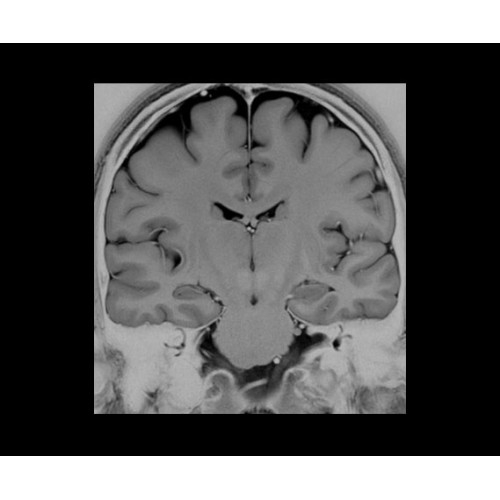

SIGNA PET/MR 3.0T — это гибридная система, в которой совмещаются две принципиально разные технологии — магнитно-резонансную томографию (МРТ) и позитронно-эмиссионную томографию (ПЭТ). Система отличающийся высокой чувствительностью и эффективностью и предназначена для диагностики в области онкологии, неврологии, кардио-васкулярных исследований, исследований воспалительных процессов.

Компания GE Healthcare представляет революционную, полностью интегрированную систему SIGNA PET/MR1, в которой сочетаются времяпролетная технология (TOF) и возможности напряженности магнитного поля 3.0 Тл. Мы поможем вам поднять исследования на более высокий уровень. SIGNA PET/MR позволяет достичь впечатляющей точности и скорости исследований, а благодаря новейшей технологии реконструкции Q.Clear2 качество изображений улучшается в два раза. Кроме того, в систему включен полный набор клинических приложений и гибких катушек для проведения любых видов исследования, открывая для вас возможности визуализации, о которых вы даже не догадывались.